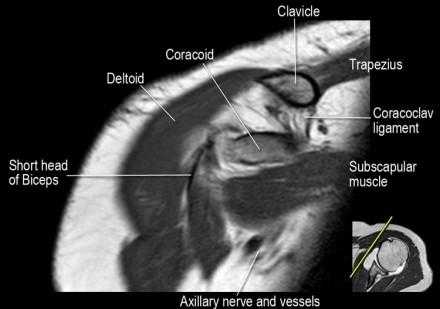

Нормальная корональная анатомия плечевого сустава и контрольный список

- обратите внимание на клюво-ключичную связку (coracoclavicular ligament) и короткую головку двуглавой мышцы (short head of the biceps).

- обратите внимание на клювоакромиальную связку (coracoacromial ligament).